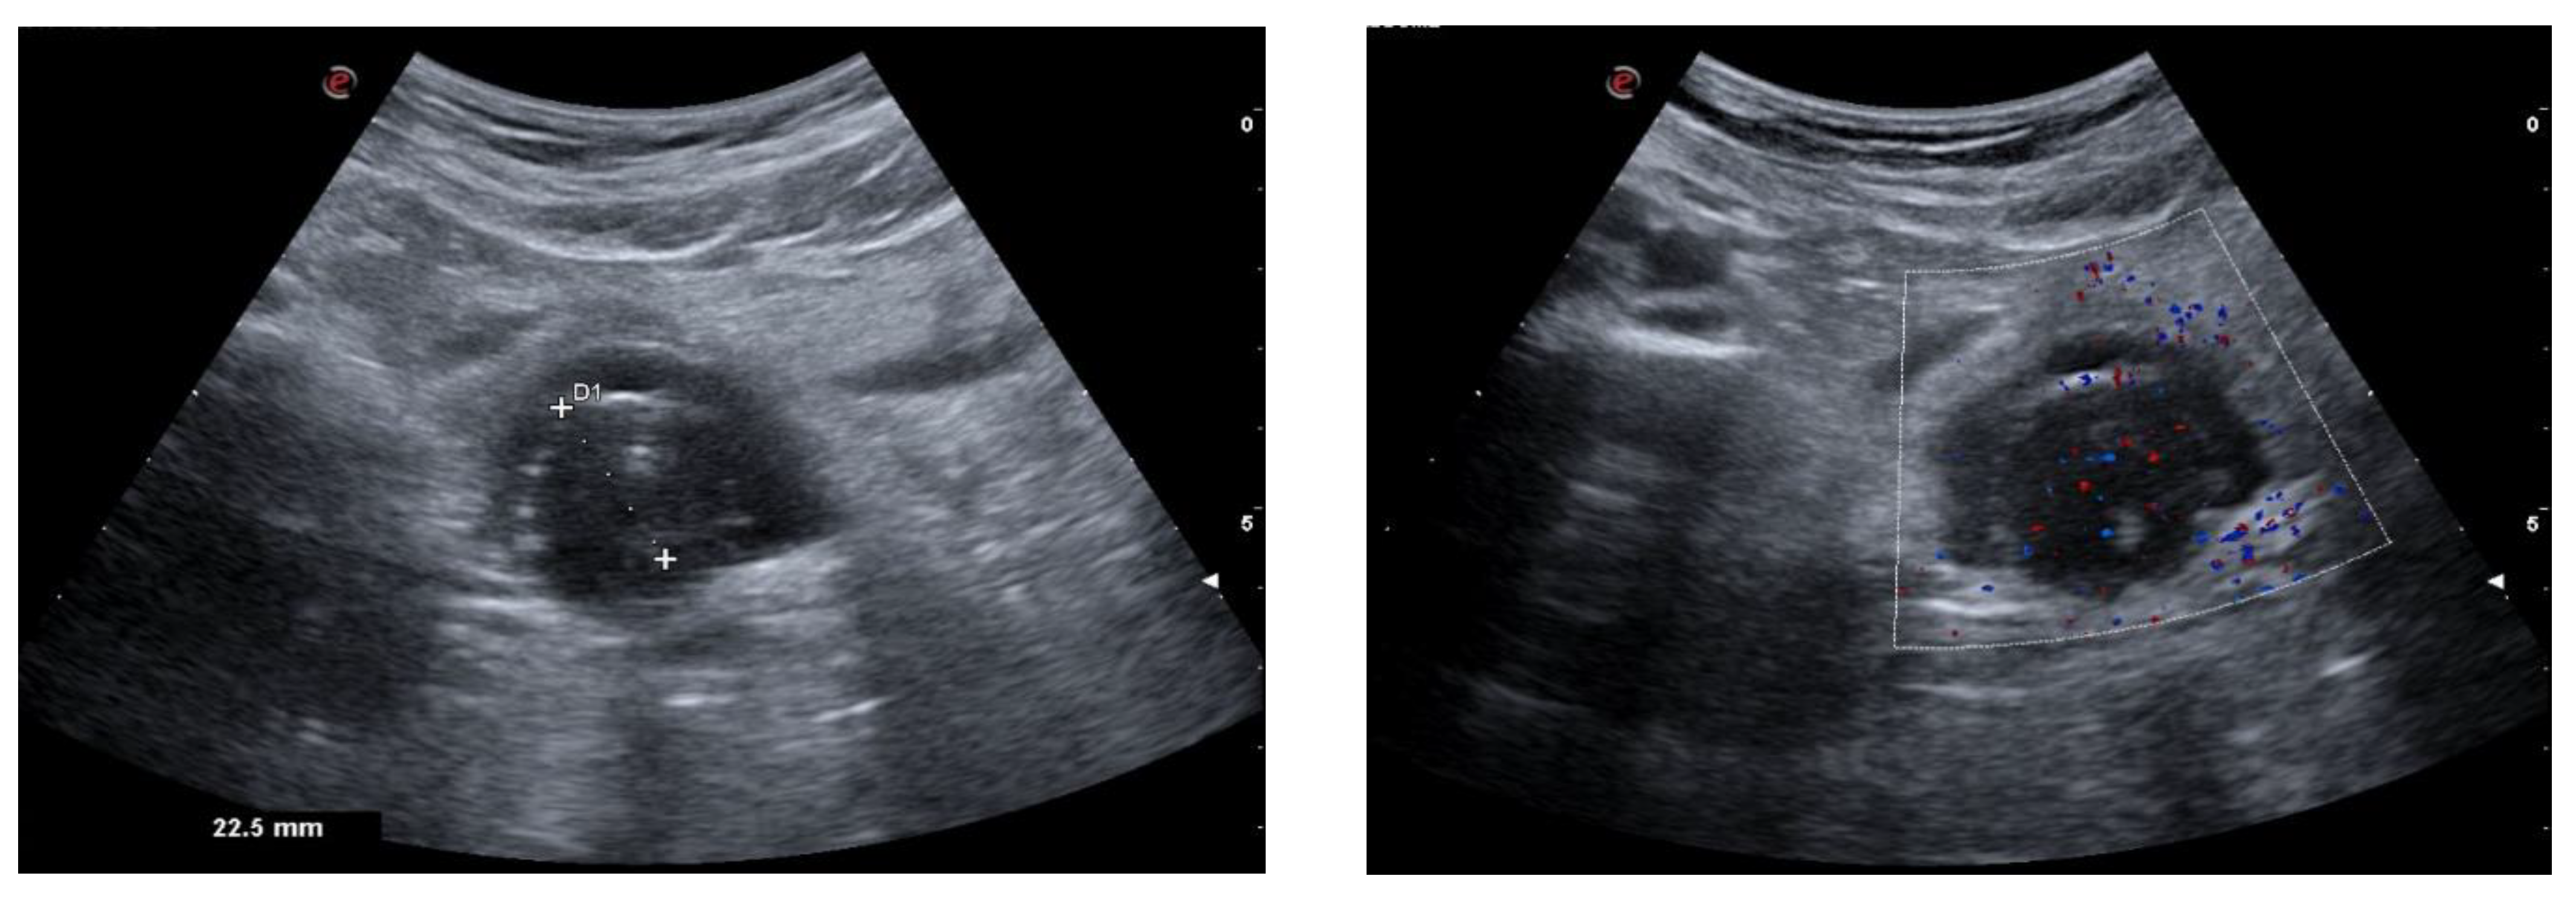

| Single cystic lesion with an echogenic nodule that leads to acoustic shadowing | Unilocular cyst with various septa and a prominent raised protuberance called “Rokitansky nodule”, containing calcifications |

| “Tip of the iceberg” sign, due to markedly echogenic areas with posterior acoustic shadowing | A marked acoustic shadowing masks the true extent of the teratoma due to presence of an echogenic focus, resulting from the presence of hair, cellular debris, fat, teeth, and calcifications |

| “Comet tail” sign | Shadowing without an echogenic focus at the tip, due to the presence of hair balls |

| Fat–fluid and fluid–fluid levels | Different echogenicity between liquid fluid, fat, and sebum |

| “Dot–dash” sign due to hyperechoic lines and dots | Different orientation of floating hair within the cyst, appearing as dots when perpendicular to the imaging plane, and dashes when parallel |

| Highly echogenic avascular mass | Poor vascularization and high presence of fat, hair, and calcifications |

| “Meat/floating balls” sign | Floating hyperechoic balls, composed of sebum, keratin, and hair balls |